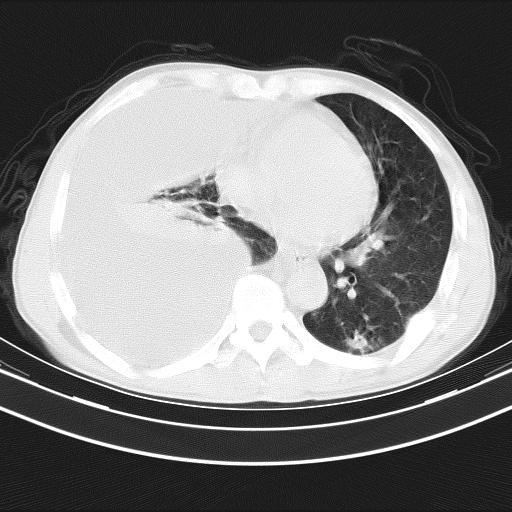

男性,44岁,结核病史多年。现胸闷气短,咳嗽,偶咳血。

右侧胸腔积液

右肺下叶不张

双肺多发结节影最分空洞形成考虑占位不除外结核

双肺陈旧性病变

1、右侧大量胸腔积液伴右肺压缩性膨胀不全,建议抽液治疗后复查 2、两肺继发性tb伴空洞形成。

1)两肺继发性肺结核伴空洞形成,左肺多发性结核球。2)右侧大量胸腔积液伴右肺部分膨胀不全。3)纵隔淋巴结肿大。